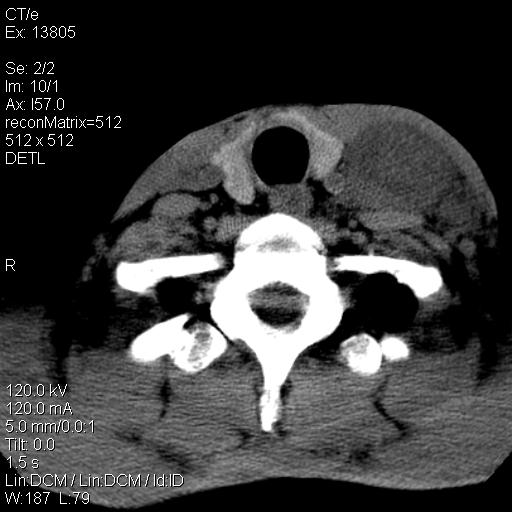

上腹部疼痛一月,呕吐10天,发现左侧颈部包快10天 胸部cr片未见明显异常。

左侧胸锁乳突肌下方、颈血管旁低密度肿块影,肿块密度尚均匀,边缘大部分清楚,邻近组织稍受压移位。考虑颈部神经鞘瘤可能性大。

颈部及腹膜后淋巴瘤可能性大